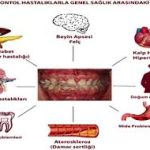

Periodontal hastalıkların kardiyovasküler hastalıklarla (KVH) ilişkisi, hem klinik hem de biyolojik düzeyde çok sayıda mekanizma üzerinden açıklanabilir. Bu ilişki genellikle sistemik inflamasyon, endotelyal disfonksiyon ve mikrobiyal etkiler üzerinden modellenir. Aşağıda temel mekanizmaları detaylı şekilde özetleyelim.

Periodontal hastalıklar, KVH riskini şu mekanizmalarla artırabilir:

| Sistemik inflamasyon | Ateroskleroz progresyonu, plaktaki instabilite |

| Bakteriyemi | Plaklarda patojen yerleşimi, lokal inflamasyon |

| Endotelyal disfonksiyon | Vazodilatasyon bozukluğu, trombosit aktivasyonu |

| Trombotik değişiklikler | Pıhtılaşma ve trombüs riski artışı |

| Moleküler taklit / immün yanıt | Otoimmün vasküler hasar |